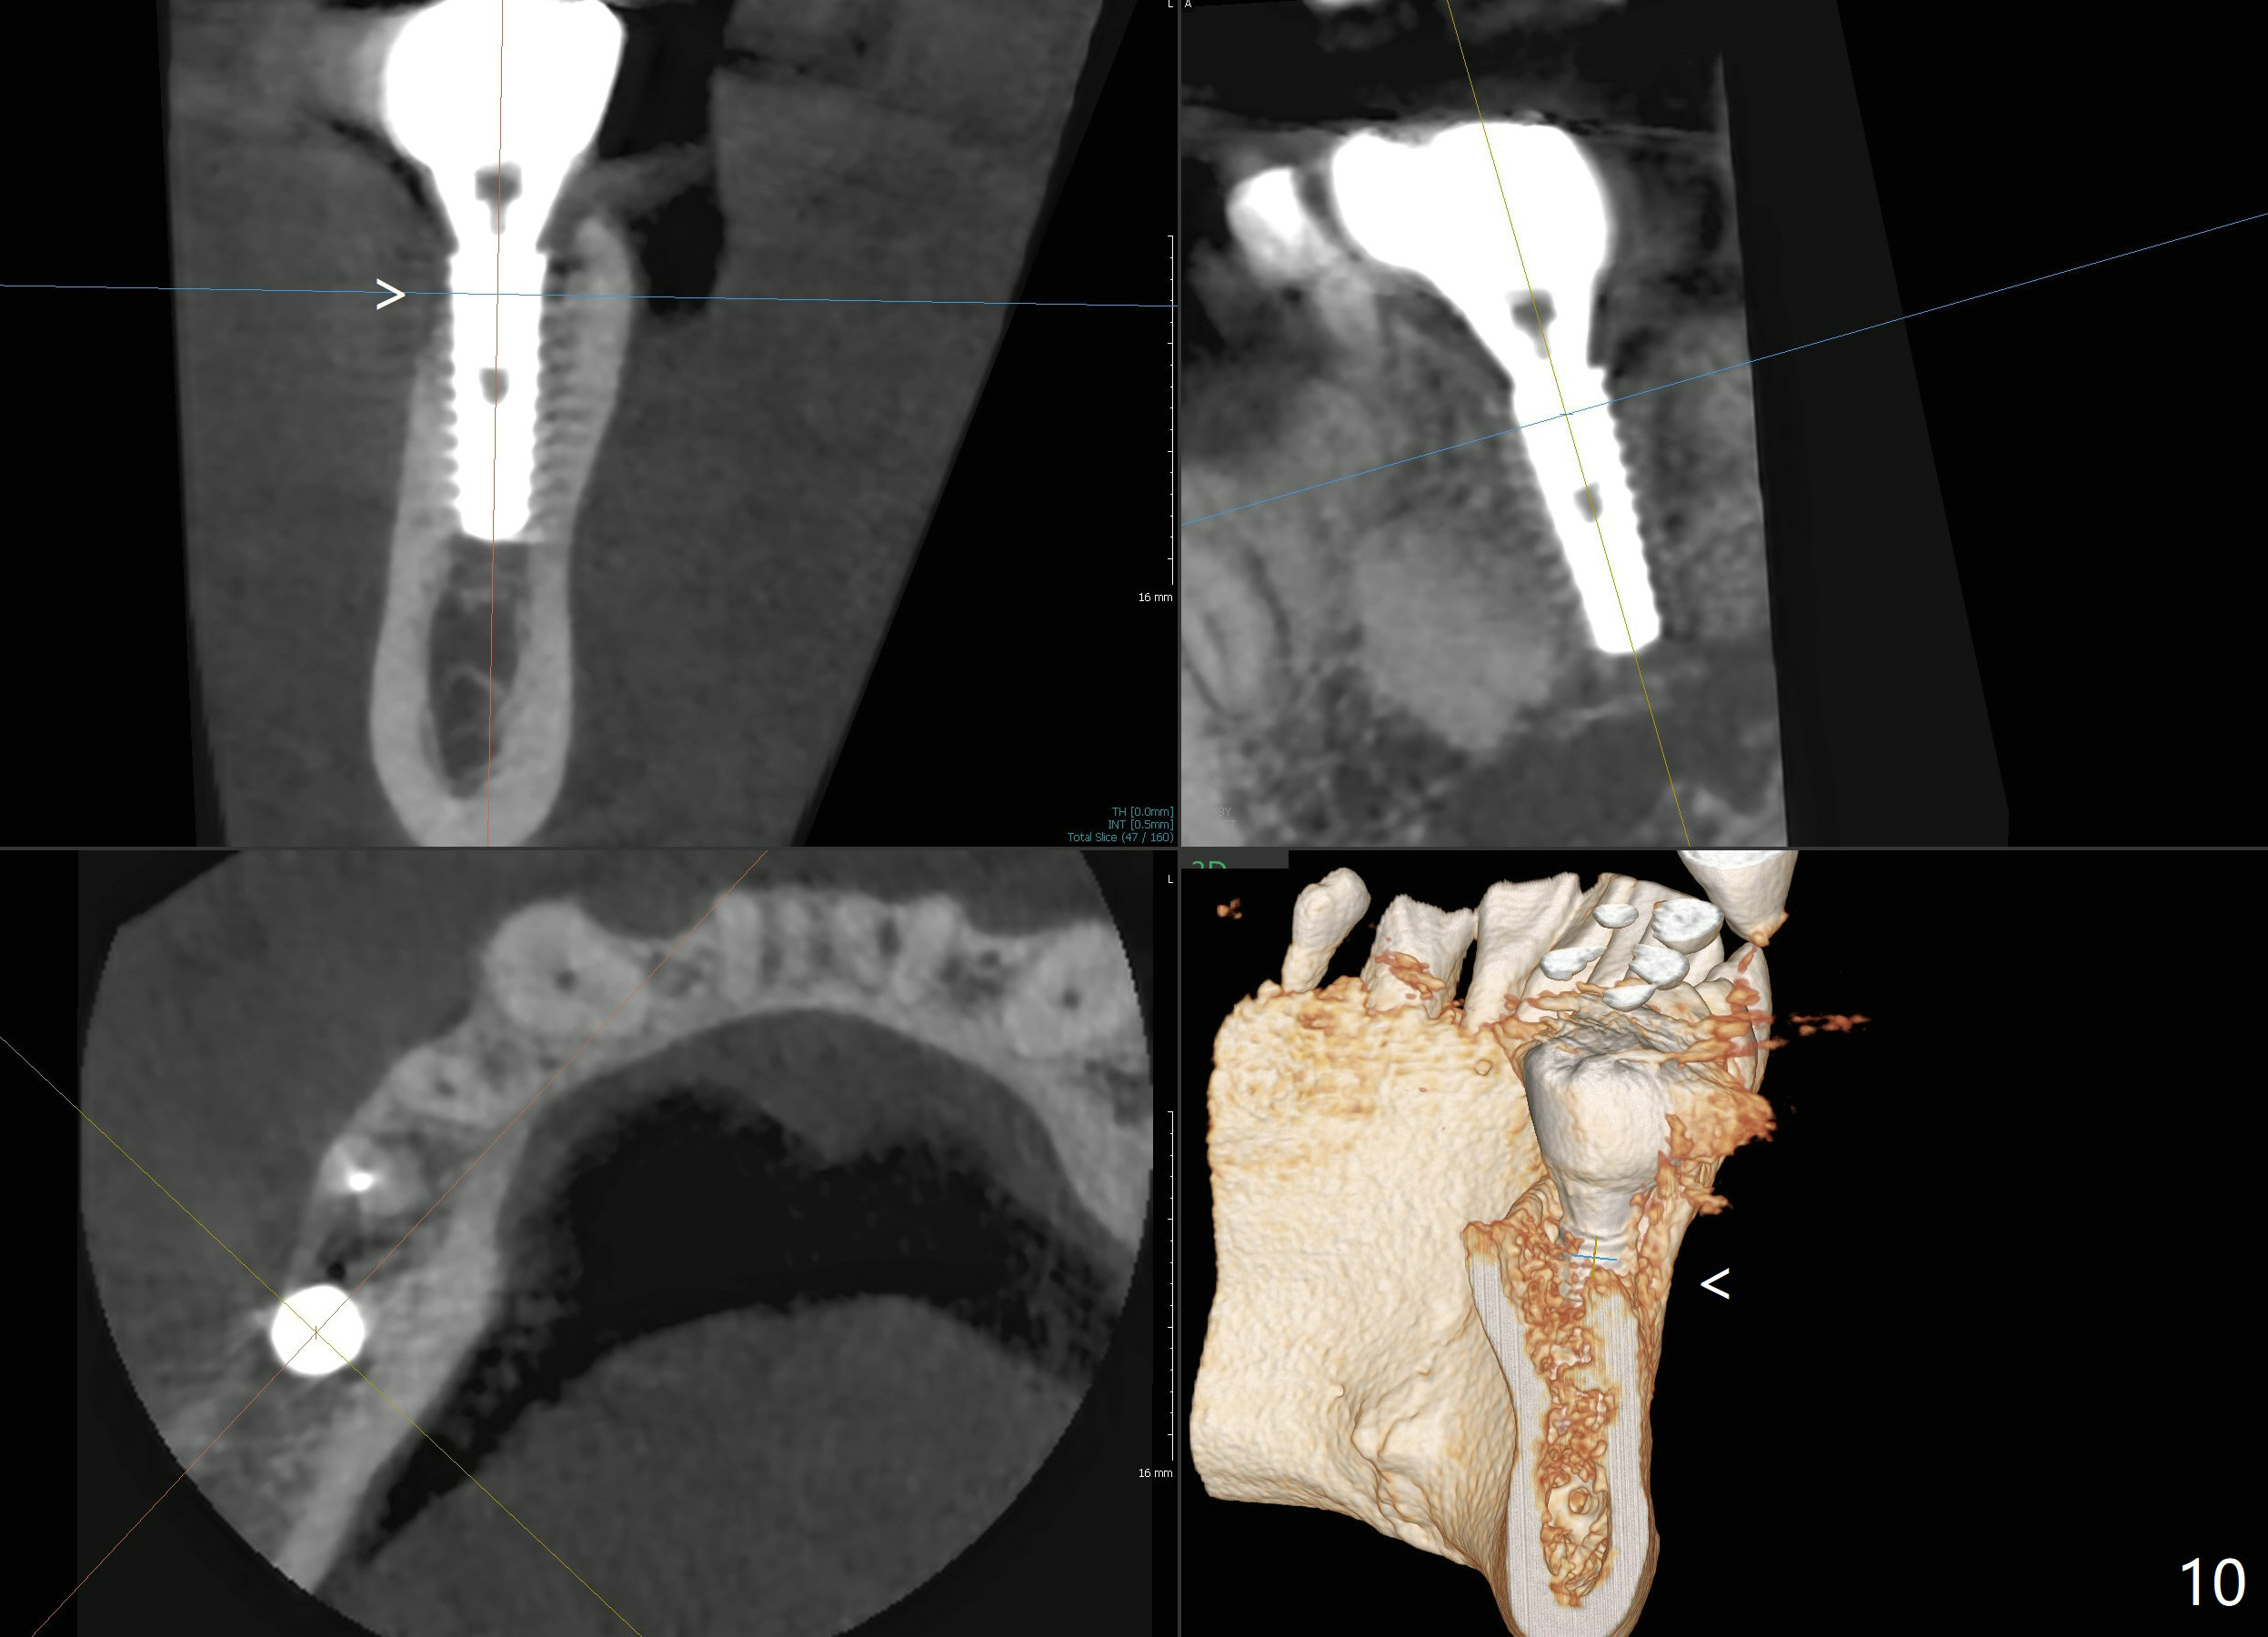

Bone graft seems to sink down and becomes denser 3 months postop (Fig.6 arrow). The bone continues being denser 5 months postop (Fig.7). There is periapical radiolucency of the tooth #29 (^). RCT is done (Fig.8). The pain persists 2 weeks postop (Fig.9,10). There is no missing canal (Fig.9). The apex is close to the implant (Fig.9 *). Apicoectomy will be performed if needed. It appears that the implant is also placed buccal (Fig.10 <) and/or the implant too large for the site. Therefore there should be a 2-3 mm buccal gap before and after implant placement. Separation and reflection of the buccal flap allows better visibility. The pain persists 1 month post RCT and 6 months post implant placement. RCT retreatment is initiated (Fig.11,12) with placement of Calcium Hydroxide paste after redebridement with 30/.04 rotary file at 23.5 mm (.5 mm longer than the earlier RCT, Fig.13). RCT retreatment finishes with apparent transportation and extrusion in 4 weeks (Fig.14,15), followed by apicoetomy (Fig.16,17) (20 days later)). Discomfort remains 2.5 months postop (Fig.18). Keep watching.